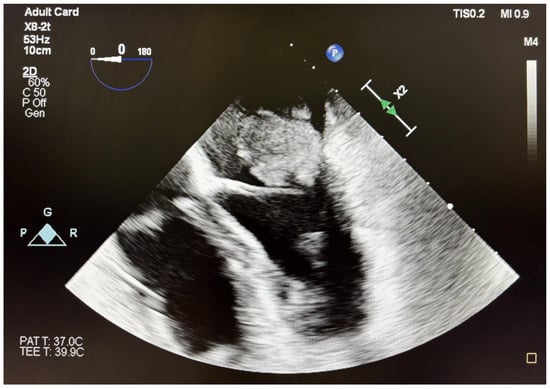

Rare Case of Grade 3 Undifferentiated Pleomorphic Sarcoma in Left Atrium, Mitral Valve, and Papillary Muscle

2. Case Report